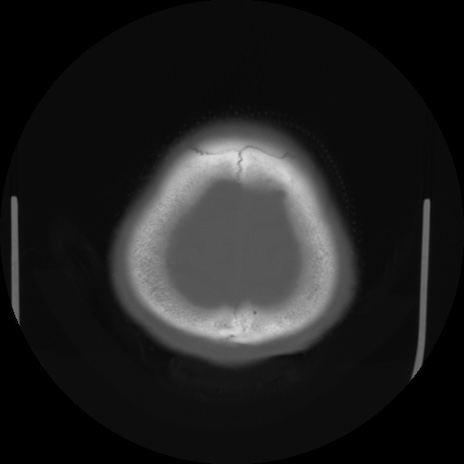

【頭部】症例5 CT(横断像)

【症例】80歳代 男性

【主訴】頭部打撲

【現病歴】外出先で椅子から立ち上がる際に、つまづいて後方へ転倒し受傷。転倒時に意識はあった。

【既往歴】高血圧、不整脈、アルツハイマー病

【身体所見】BP 217/71、HR 96、JCS1-1、 難聴あり、顔色良好、右後頭部に擦過創あり。神経学的異常なし。

症例5の画像所見と診断は?